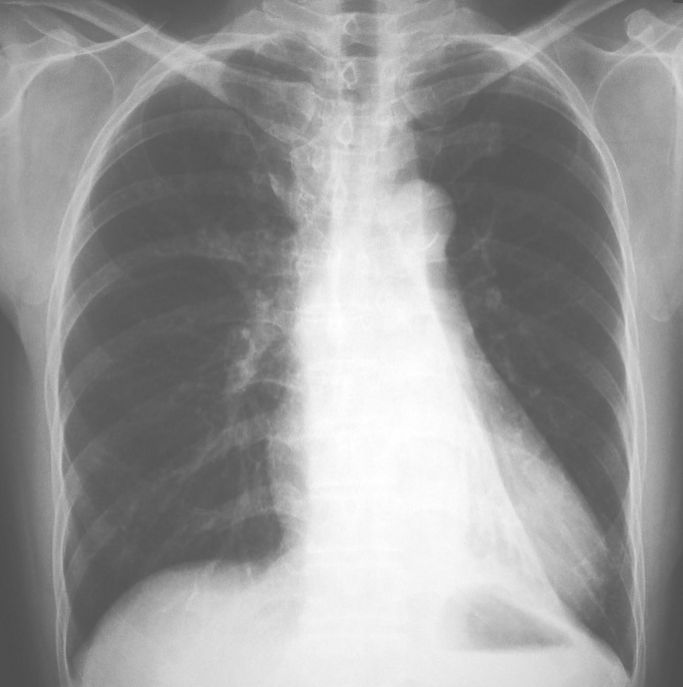

3. 一位60歲男性,長期咳嗽有痰,走路時會喘,聽診顯示左肺呼吸音較小,胸部X光如圖所示。請問他罹患何種疾病?

(A) 氣管狹窄 (B) 心臟衰竭 (C) 左肺氣腫 (D) 左肺下葉扁塌 (E) 氣喘病